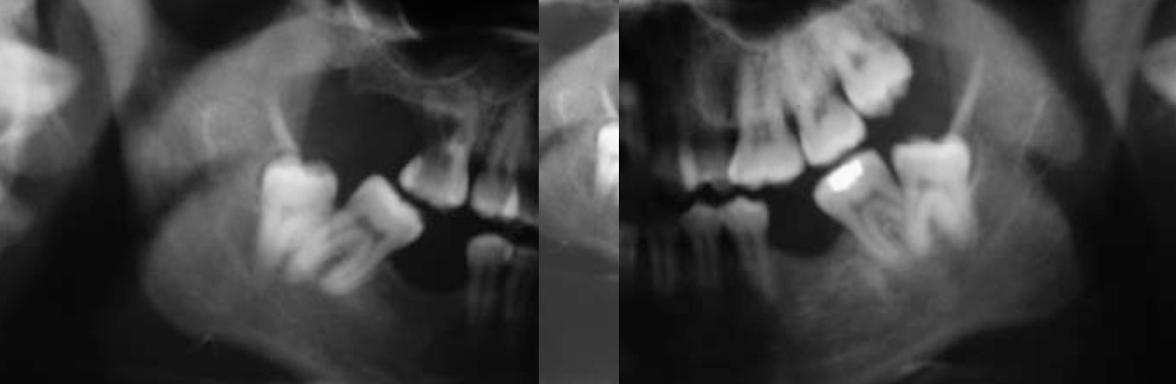

What dental anomaly is this?

Taurodontism